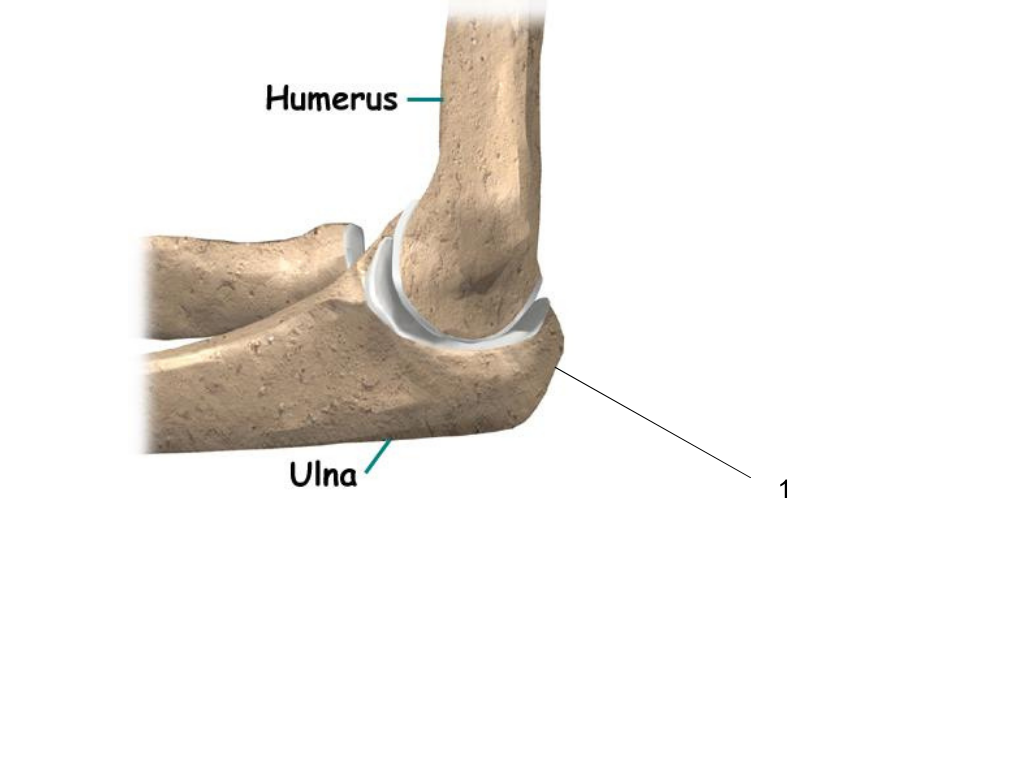

olecranon process

what is #1 pointing at?